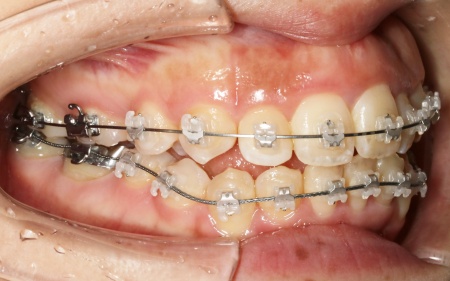

続いて、上下の歯の表面に金属のブラケットよりも目立ちにくい「セラミックブラケット」を接着し、ワイヤー矯正を開始しました。

ワイヤー矯正である程度歯並びが整ったら、マウスピース矯正に移行します。